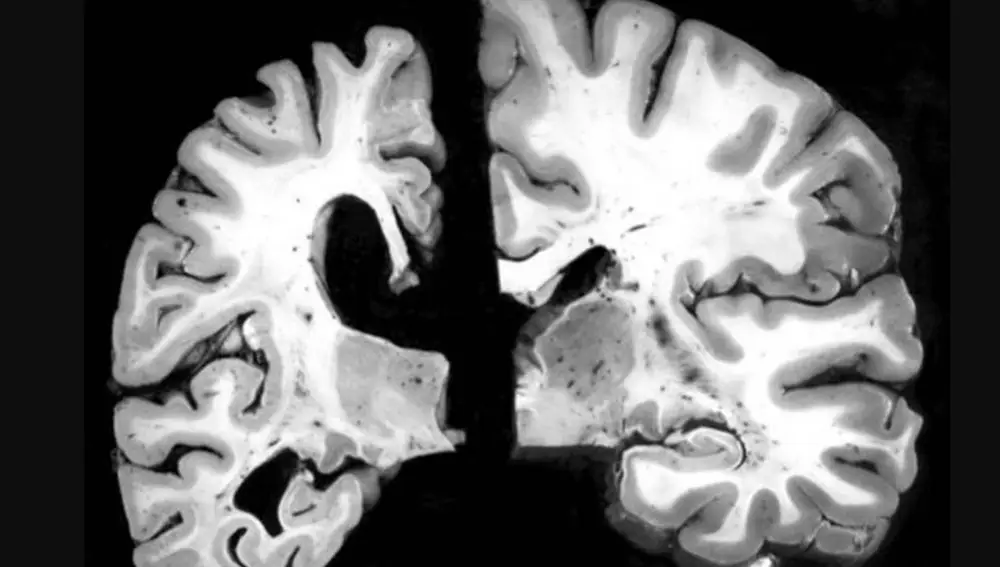

El impacto de esta enfermedad es progresivo, pero devastador. El Alzheimer afecta las células nerviosas que funcionan como mensajeros entre el cerebro y el resto del cuerpo. Cuando las conexiones entre estas células se ven afectadas por el Alzheimer, se generan serios problemas en nuestra capacidad para pensar, planificar, razonar y recordar. Por esta razón, uno de los primeros síntomas del Alzheimer es la pérdida de memoria, especialmente de la memoria reciente. Las personas que padecen esta enfermedad pueden olvidar con facilidad eventos recientes o tener dificultades para recordar nombres de personas u objetos comunes.